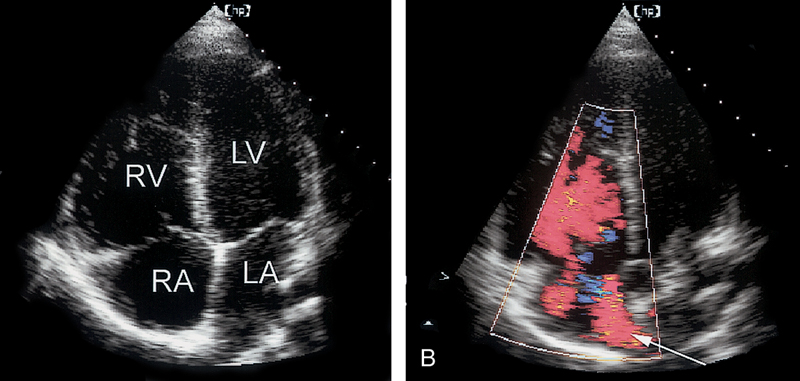

فحوصات تشخيصية لبعض امراض القلب والشرايين التاجية